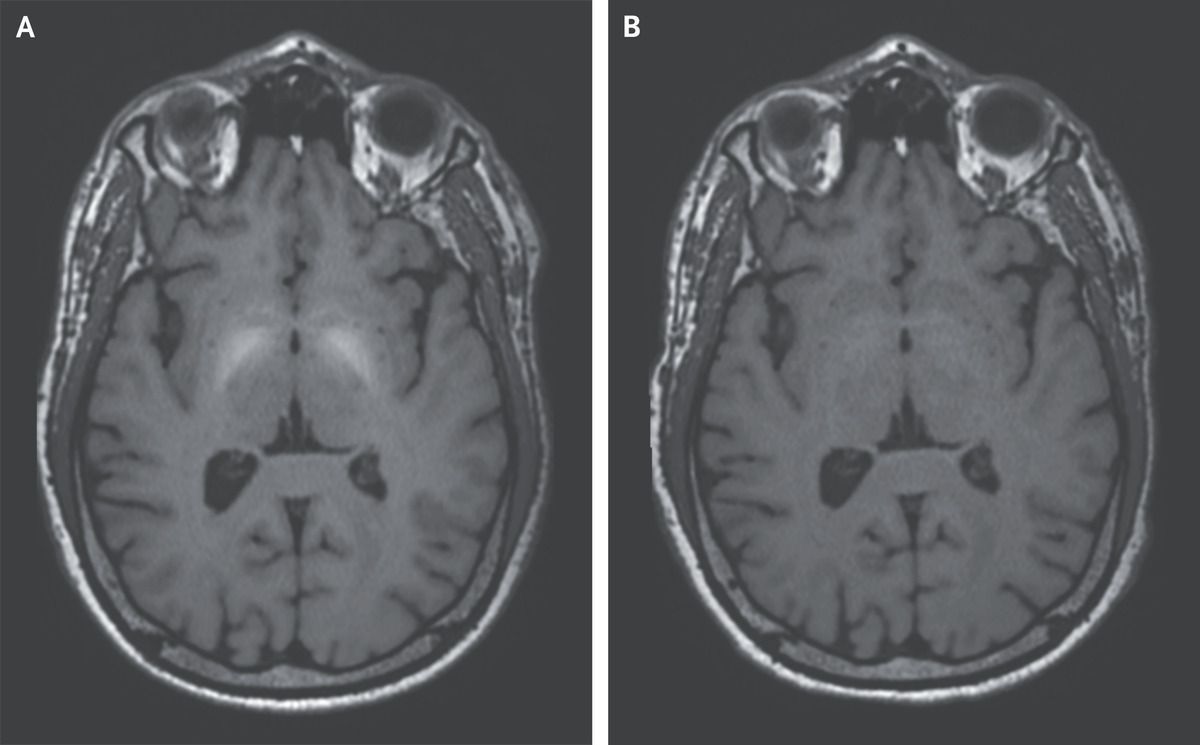

A 55-year-old man presented to the neurology clinic with a 10-year history of progressive handwriting impairment and rapid, slurred speech. In his thirties, he had worked as a welder without access to personal protective equipment. Neurologic examination was notable for reduced facial expression, blepharospasm, and cluttered, dysarthric speech. The patient’s handwriting was disorganized and micrographic. Postural reflexes were mildly impaired. The patient’s occupational exposure, parkinsonism, and blepharospasm aroused concern for toxic effects from exposure to heavy metals. Subsequent magnetic resonance imaging (MRI) of the head showed a nonenhancing, T1-weighted, hyperintense signal in the basal ganglia on both sides (Panel A). Results of laboratory tests, including a serum iron panel and measurements of ceruloplasmin and urinary copper excretion, were normal. On the basis of the patient’s welding history and neurologic syndrome, a diagnosis of manganese poisoning was made. Serum and urine manganese levels were not obtained, since these values are often normal in cases of chronic or previous exposure. Whole-exome sequencing did not identify an inherited error in manganese metabolism. Treatment with intravenous EDTA was administered for 6 months, and the patient’s symptoms subsequently abated and the abnormal findings on MRI resolved (Panel B).